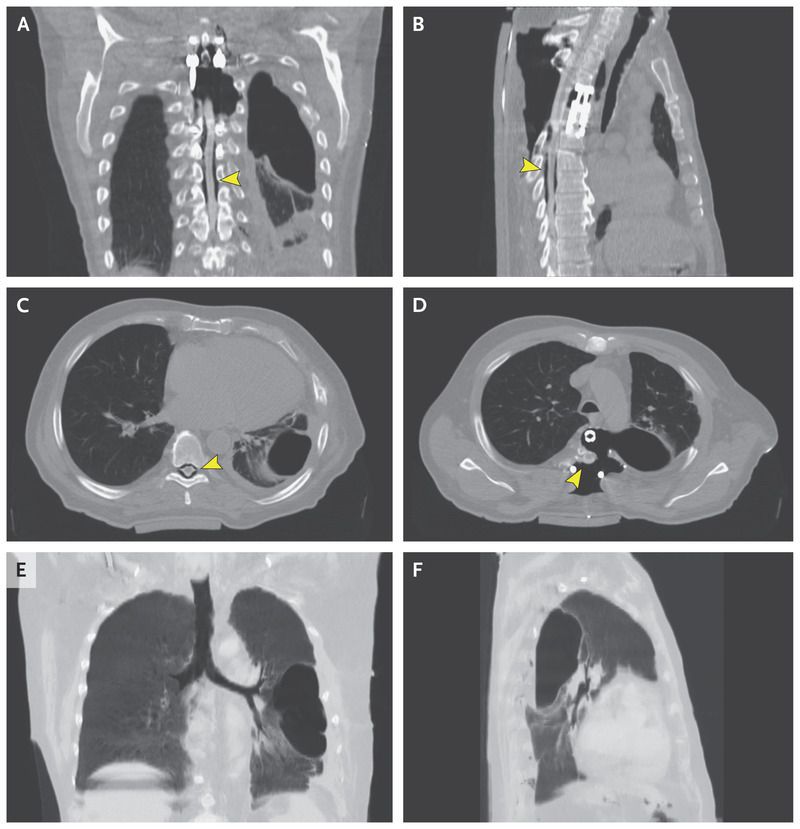

A 65-year-old man was admitted to the hospital to undergo adjuvant radiotherapy after having previously undergone tumor mass reduction and anterior and posterior stabilizing spinal surgery for a synovial sarcoma. On physical examination, ballooning of the right paravertebral area was noted, which increased when the Valsalva maneuver was performed (see video). The phenomenon was caused by a pneumothorax that developed after the surgical procedure and propagated along the anterior and posterior surgical approaches. The entrapped air gained access to the epidural space, which led to extensive pneumorrhachis (Panels A through D, arrowheads) and to subcutaneous emphysema (Panels B and D). Pneumothorax is diagnosed in 3 to 5% of patients who undergo spinal surgery along the anterior approach and is usually caused by small pleural injuries. In our patient, no injury of the large airways was present (Panels E and F). The patient underwent revision surgery and started radiotherapy 3 weeks after the procedure; no further complications occurred. At a 6-month follow-up visit, the patient had complete remission of the sarcoma and had not had a recurrence of pneumothorax or pneumorrhachis.